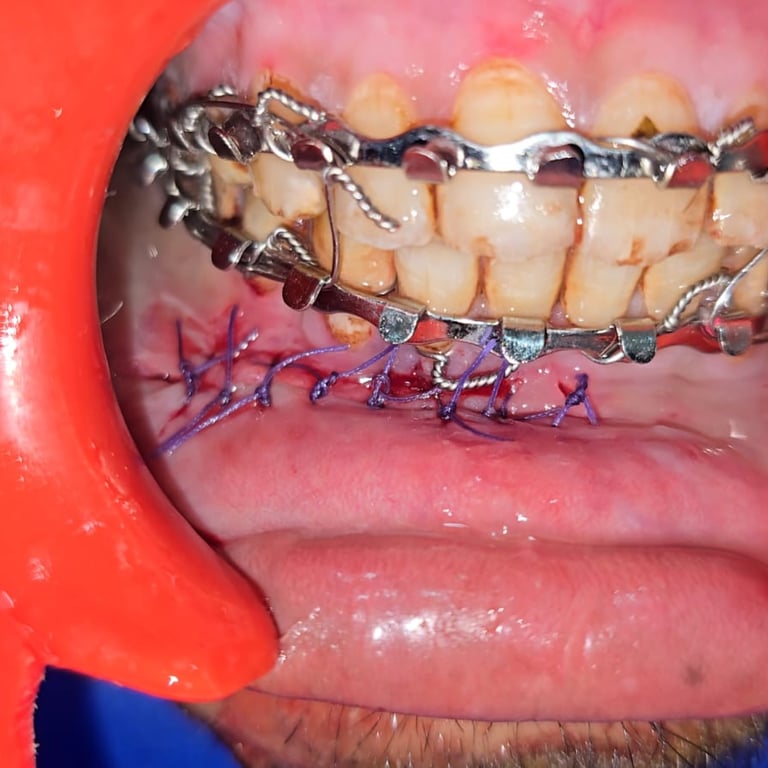

Surgery & Recovery

See how we treated a parasymphysis mandibular fracture in an 18-year-old male using IMF & plating. Scar-free recovery in just 15 days.